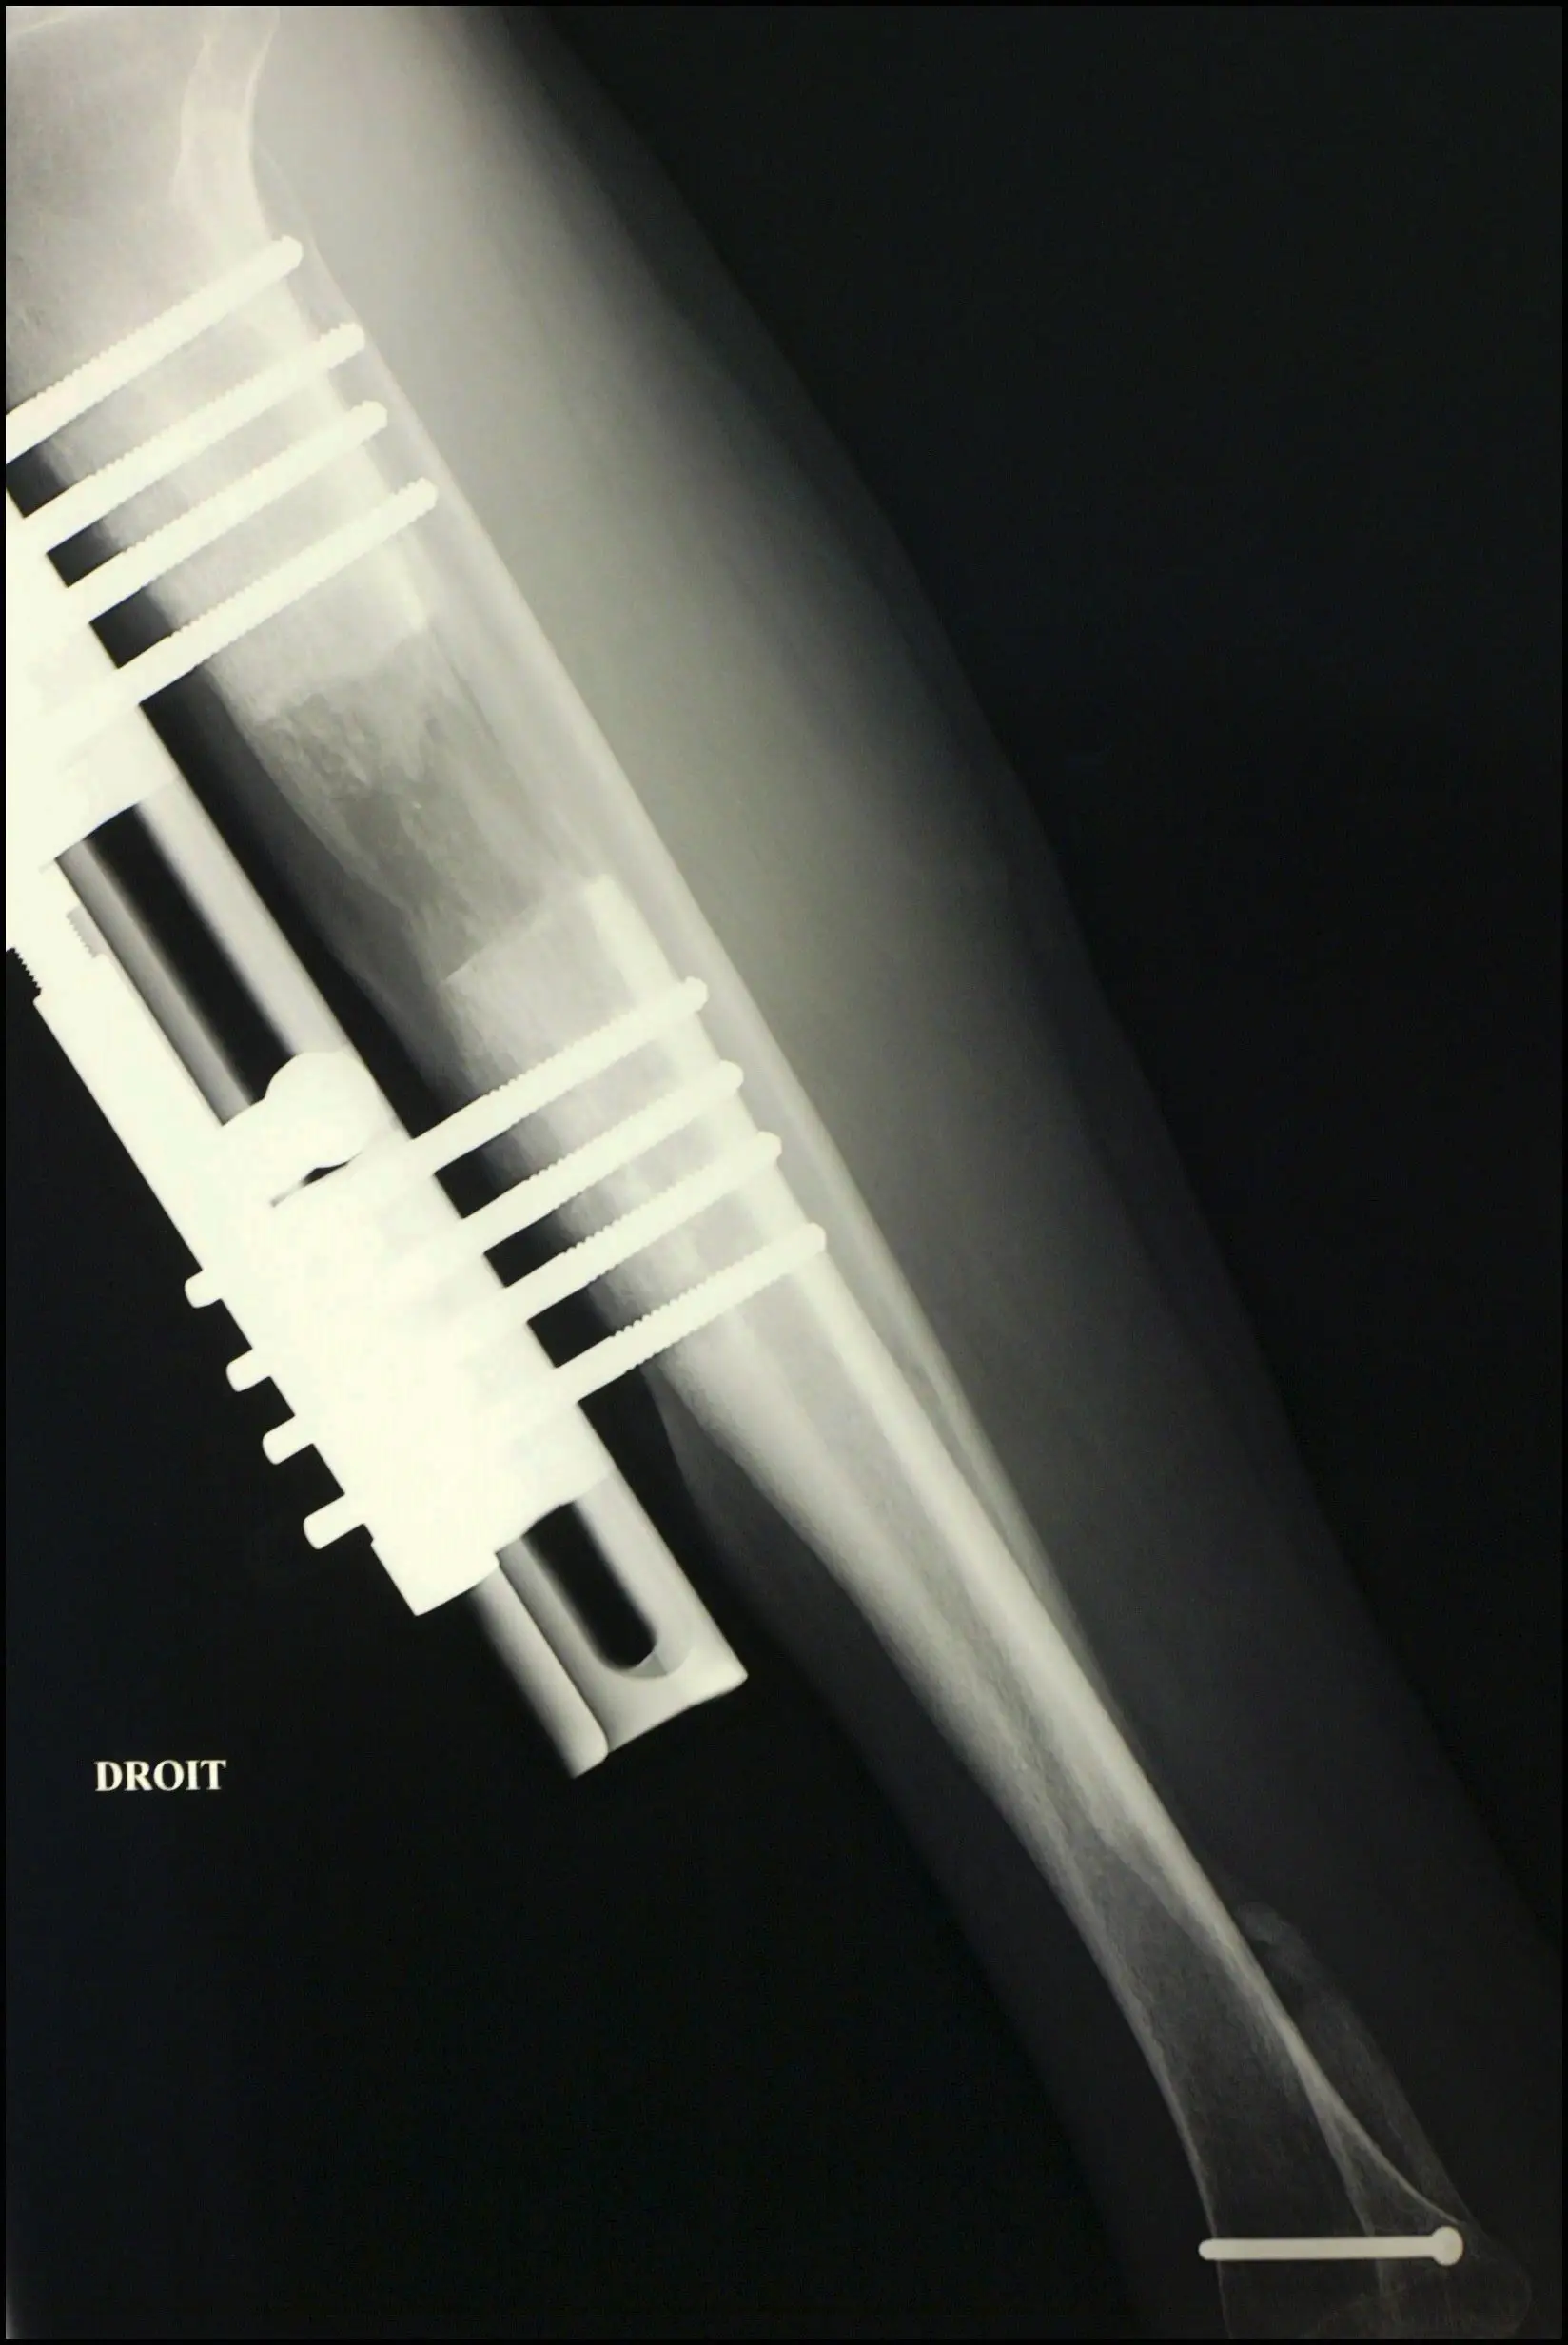

Things get off to a strong start when the bones in the thighs are broken. A series of metal pins and braces are then implanted to the area around the break with a little screw sticking out.

Over the next few weeks the patient has to turn the screw a set amount each day. This gradually stretches out the leg as the bone is healing.